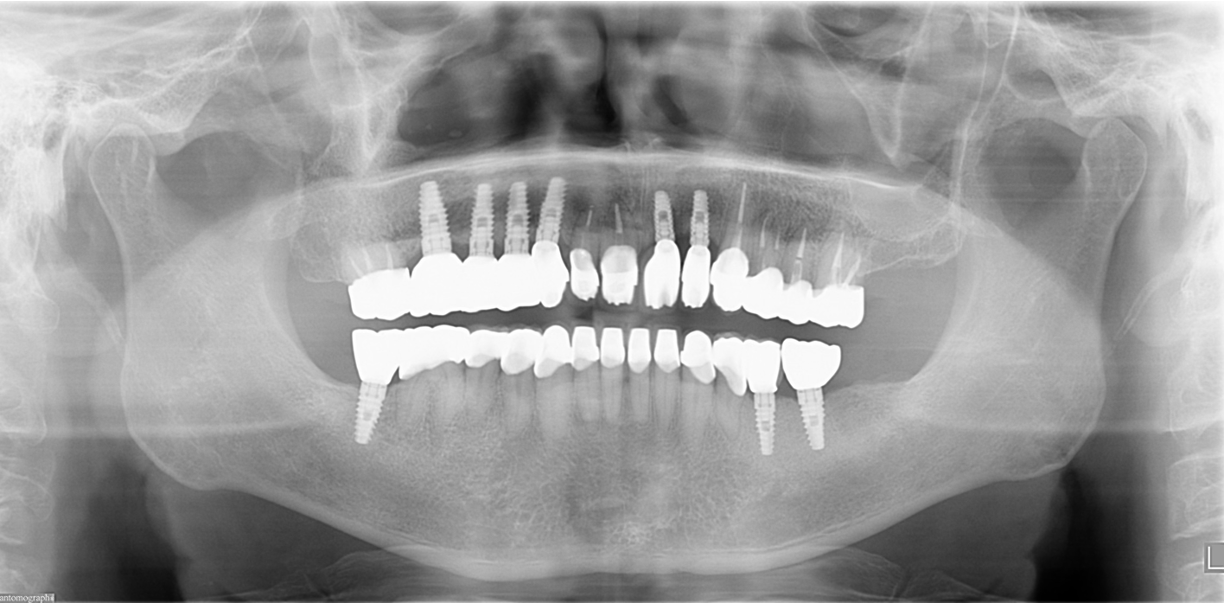

| 主訴 | 全顎治療希望、全顎的に歯が動く、奥の歯がなくて噛めない。できるだけ綺麗で噛めるようになりたい。 |

| 治療内容 | 全顎的に歯周病、前歯部の被蓋が深く、重度歯列不正が認められるため、 歯周外科を含む歯周治療、矯正治療、インプラント治療、セラミックによる補綴治療後メインテナンスに移行しました。 |

| 治療費 | 5,060,000円(税込)(インプラントすべて含む) |

| 治療期間 | 2年4ヶ月 |

| 治療回数 | 90回 |

| 想定されたリスク | 矯正治療の後戻り、歯周病の再発、食いしばり(パラファンクション)によるセラミックの破折、歯の破折のリスクがありました。 |